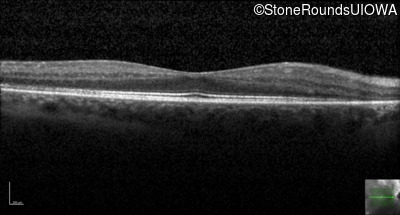

Optical Coherence Tomography - Right - 20/32 +2 sc

Exemplar / OCT Stack

OCT Stack